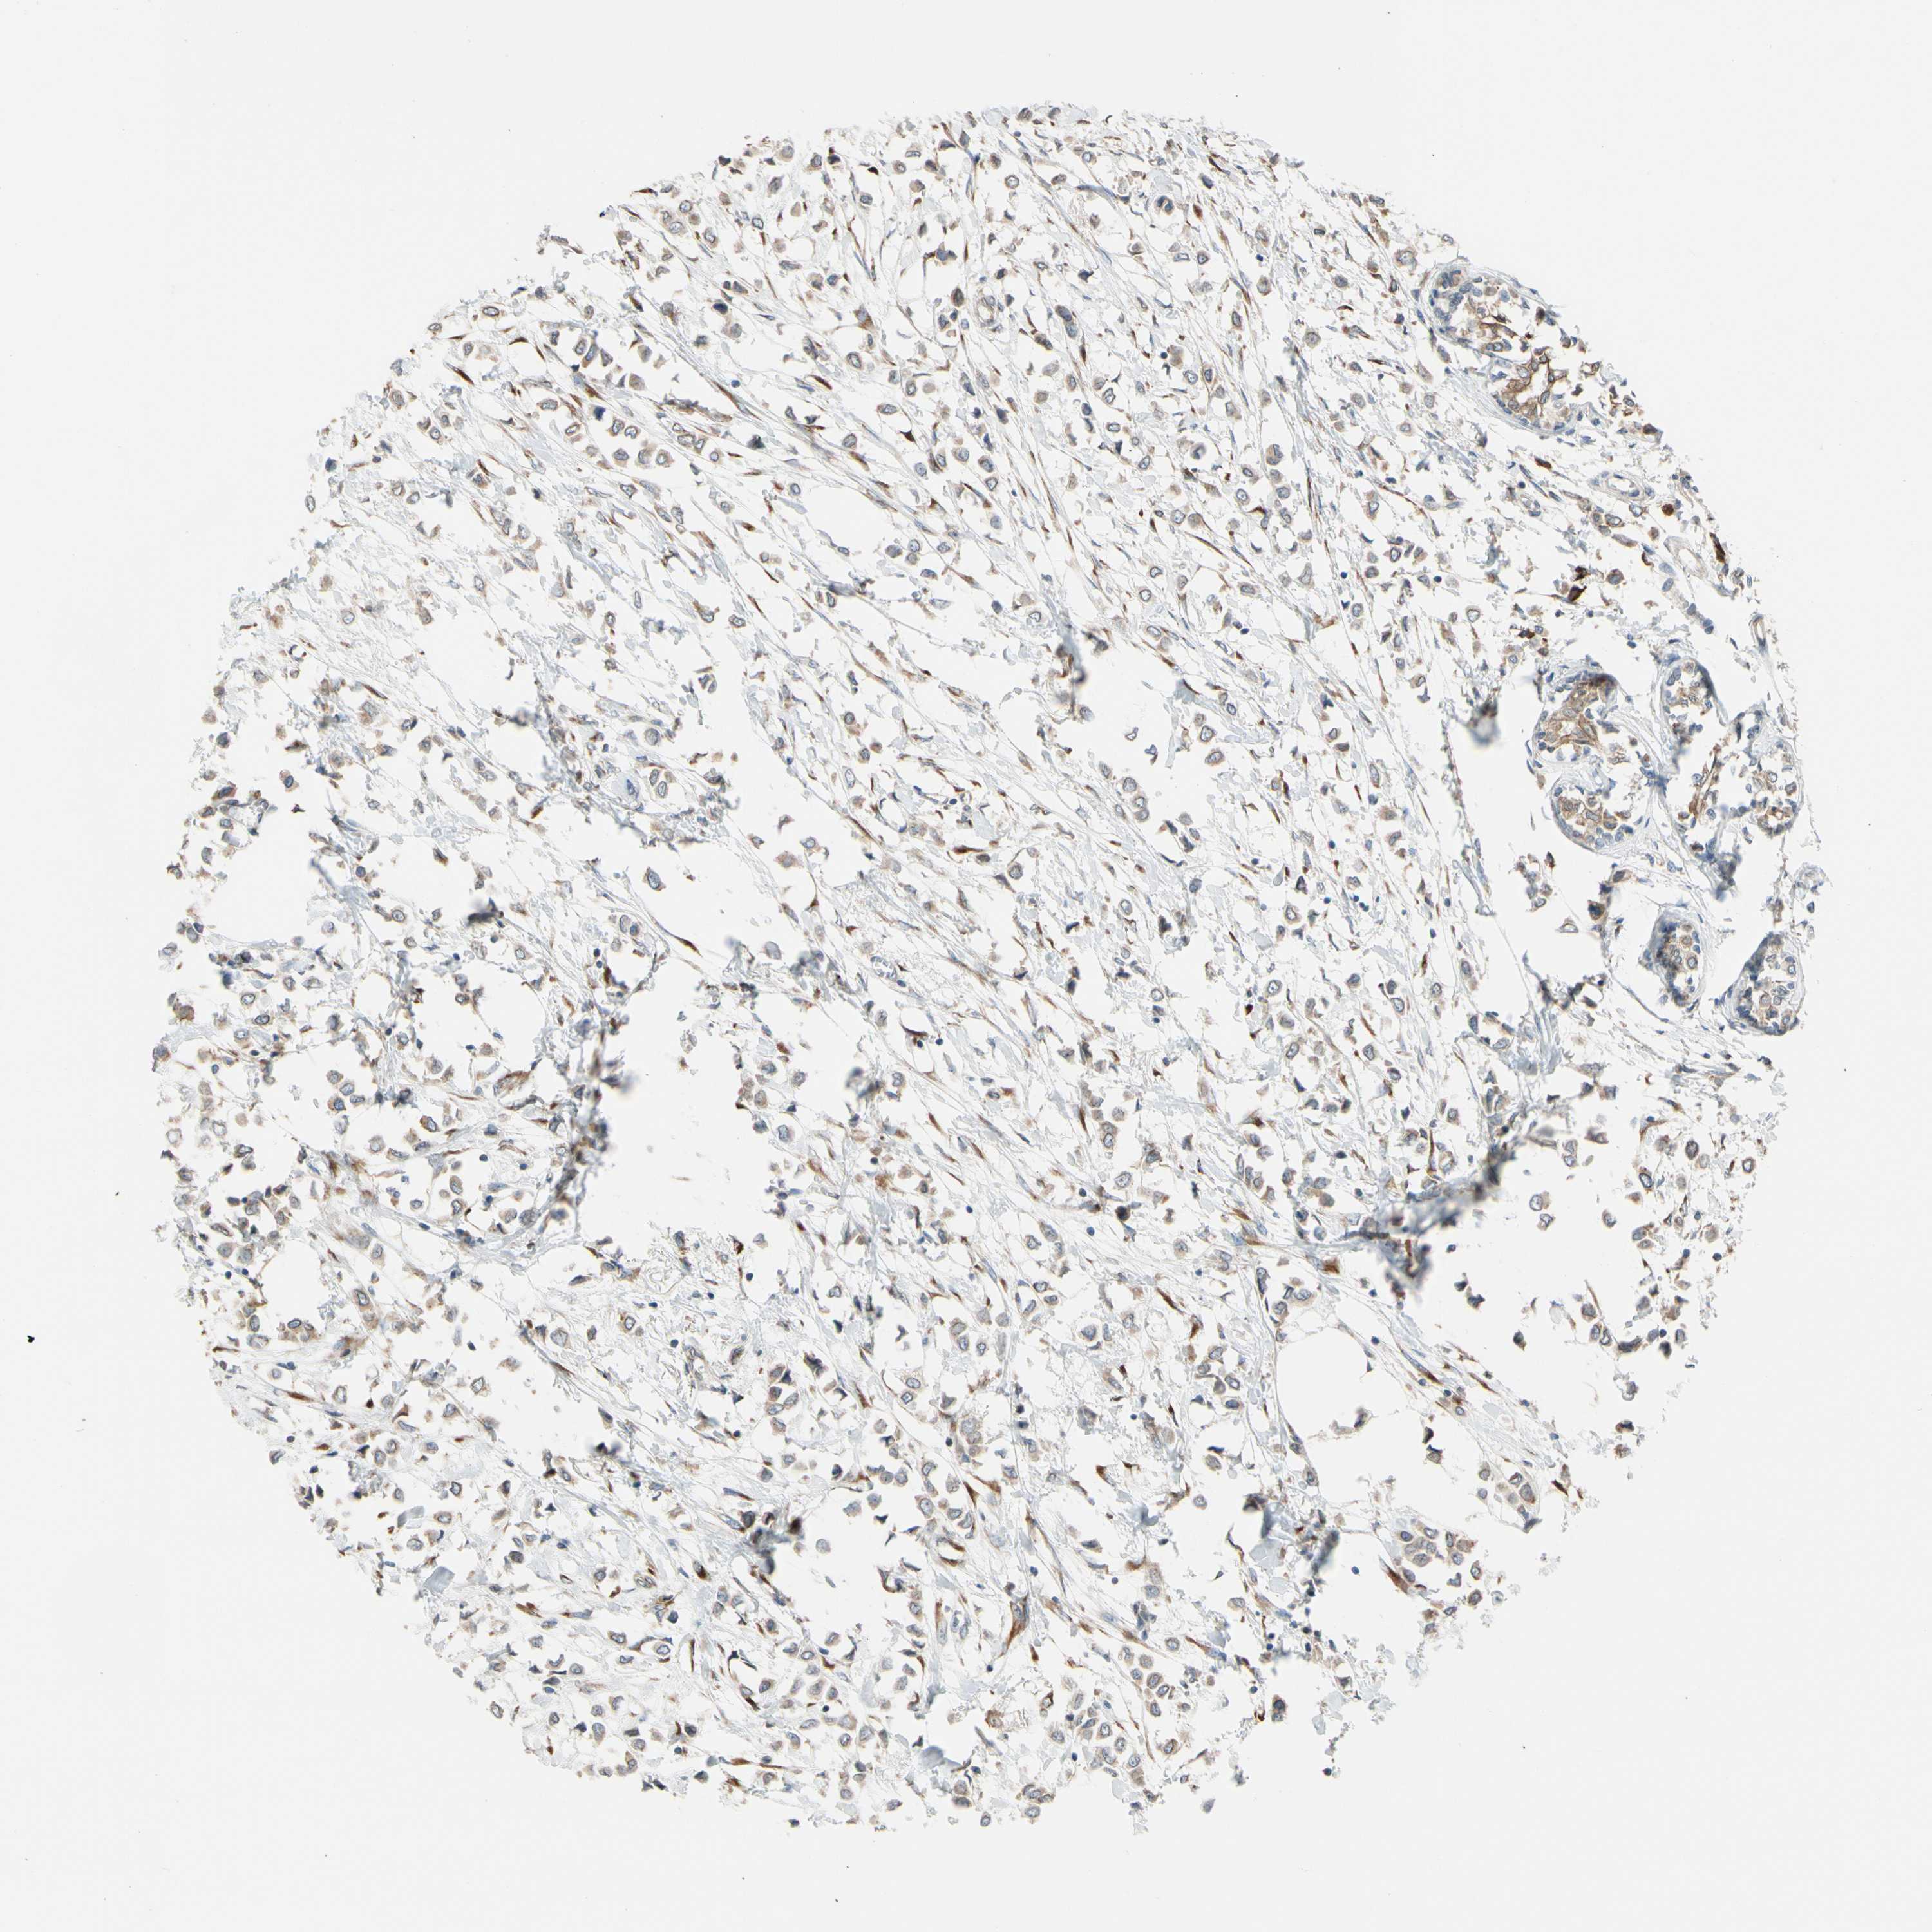

CANCER BREAST CANCER Show tissue menu

BRCA TCGA BRCA VALIDATION PROTEIN EXPRESSION

Breast cancer

Human cancer